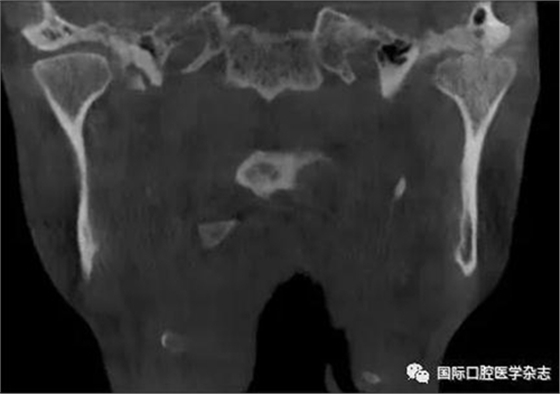

(3)骨關(guān)節(jié)病(圖2):屬于顳下頜關(guān)節(jié)器質(zhì)性改變,主要發(fā)生在髁突的骨質(zhì)變化,其次是關(guān)節(jié)窩及關(guān)節(jié)結(jié)節(jié)的改變。影像學(xué)檢查發(fā)現(xiàn)骨、軟骨和關(guān)節(jié)盤有退行性改變,關(guān)節(jié)運(yùn)動(dòng)時(shí)可聞及連續(xù)摩擦音。伴有滑膜炎或關(guān)節(jié)囊炎時(shí),有開口痛和咀嚼痛,開口受限,這時(shí)可稱骨關(guān)節(jié)炎。

圖 2 骨關(guān)節(jié)病